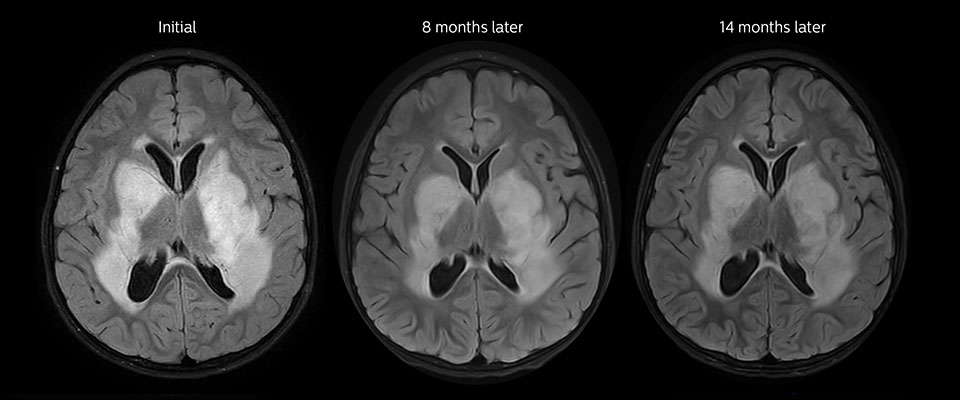

APT imaging of low-grade tumor

Low-grade glioma in a 5-year-old patient with neurofibromatosis 1. This low-grade lesion does not enhance on the post-contrast images, but does show an intermediate APT signal. The lesion stability over time confirms that it is a low-grade pathology.

Follow-up over time

Follow up results